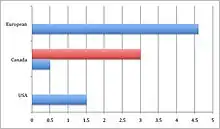

OBPP, also known as obstetrical brachial plexus palsy, occurs primarily in young children at a rate of 0.38 to 1.56 per 1000 live births depending on the type of care and the average birth weight of infants in different regions of the world.[37] For example, a study in the United States showed and incidence of OBPP of about 1.51 cases per 1000 live births, in a Canadian study, the incidence was between 0.5 and 3 injuries per 1000 live births, a Dutch study reported an incidence of 4.6 per 1000 live births.[37] The risk of BPI at birth is highest for infants weighing more than 4.5 kg at birth born to diabetic women. Type of delivery also affects the risk of BPI.[39] Brachial plexus injury risks for newborns are increased with gained birth weight, birth delivery where a vacuum is assisted, and not being able to handle glucose.[40]